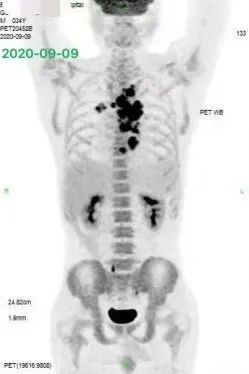

进一步完善 PET-CT:提示病灶累及胸椎、右上纵隔内、气管下段、左右主支气管周围、隆突下、右肺门多发淋巴结、胃小弯 (2.9 cm*2.6 cm)、右中下腹肠系膜多发淋巴结肿大伴代谢增高 (4.6 cm*3.7 cm);右侧闭孔内肌条等位置。临床分期 IVB 期。如下图 1: